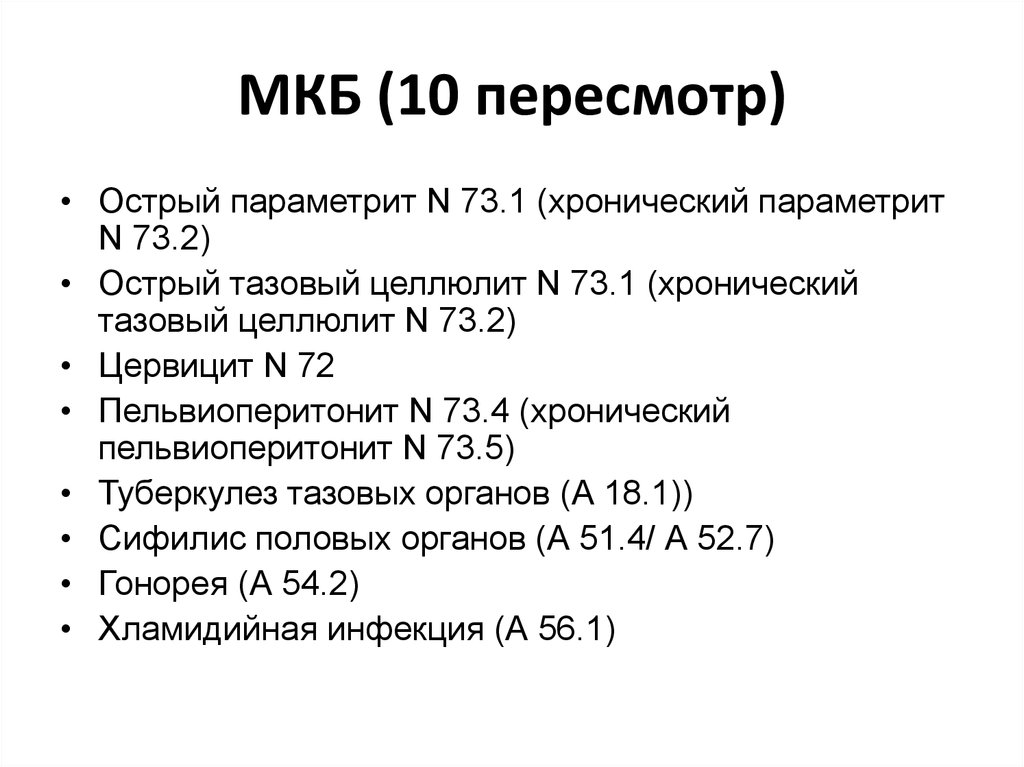

Код мкб 10 атерома головы

Код мкб 10 атерома головы 109 фото